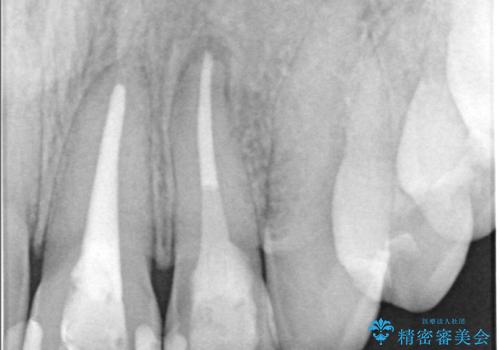

左上1番および2番は失活歯であり、両歯ともに失活に伴う変色を認めました。左上2番に関しては根尖部に透過像を認め、根尖性歯周炎と診断しました。これが前歯部の痛みの原因と考えられました。

左上2番に対して精密根管治療を実施し、感染源の除去を行いました。その後、左上1、2番ともにオールセラミッククラウンによる補綴を行い、審美的な修復を行いました。

根管治療では、ラバーダム、マイクロスコープ、根管をしっかり洗浄するための専用器具の使用が必須となる治療です。

徹底した洗浄により高い治療効果が得られます。